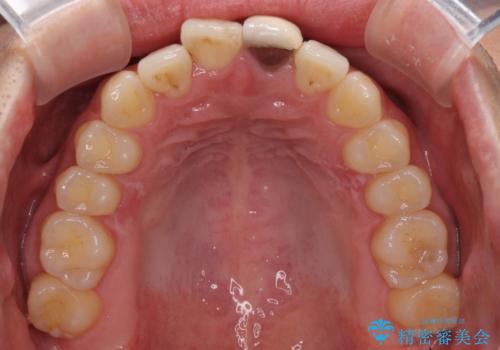

前歯の歯並びとクラウンを改善 インビザラインとオールセラミック

- 前歯の歯並びと不自然な色をした前歯のクラウンを気にして来院された患者様です。

上下前歯の歯列不正はインビザラインにより歯列を整え、その後に、前歯をオーダーメイドタイプのオールセラミッククラウンにて補綴治療することとしました。

初診時には、歯並びを整えることのみを検討されていましたが、歯列が整うにつれて不自然な色合いが気になるようになり、矯正治療を行ってから補綴治療をする計画を受け入れてくださいました。